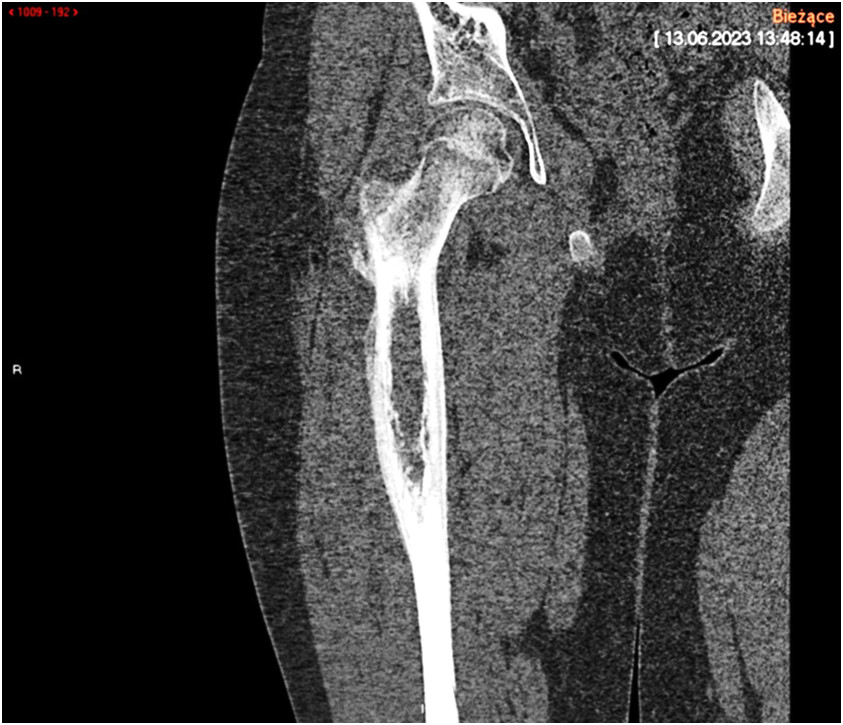

rzedstawiony radiogram wskazuje na złamanie okołoprotezowe typu: